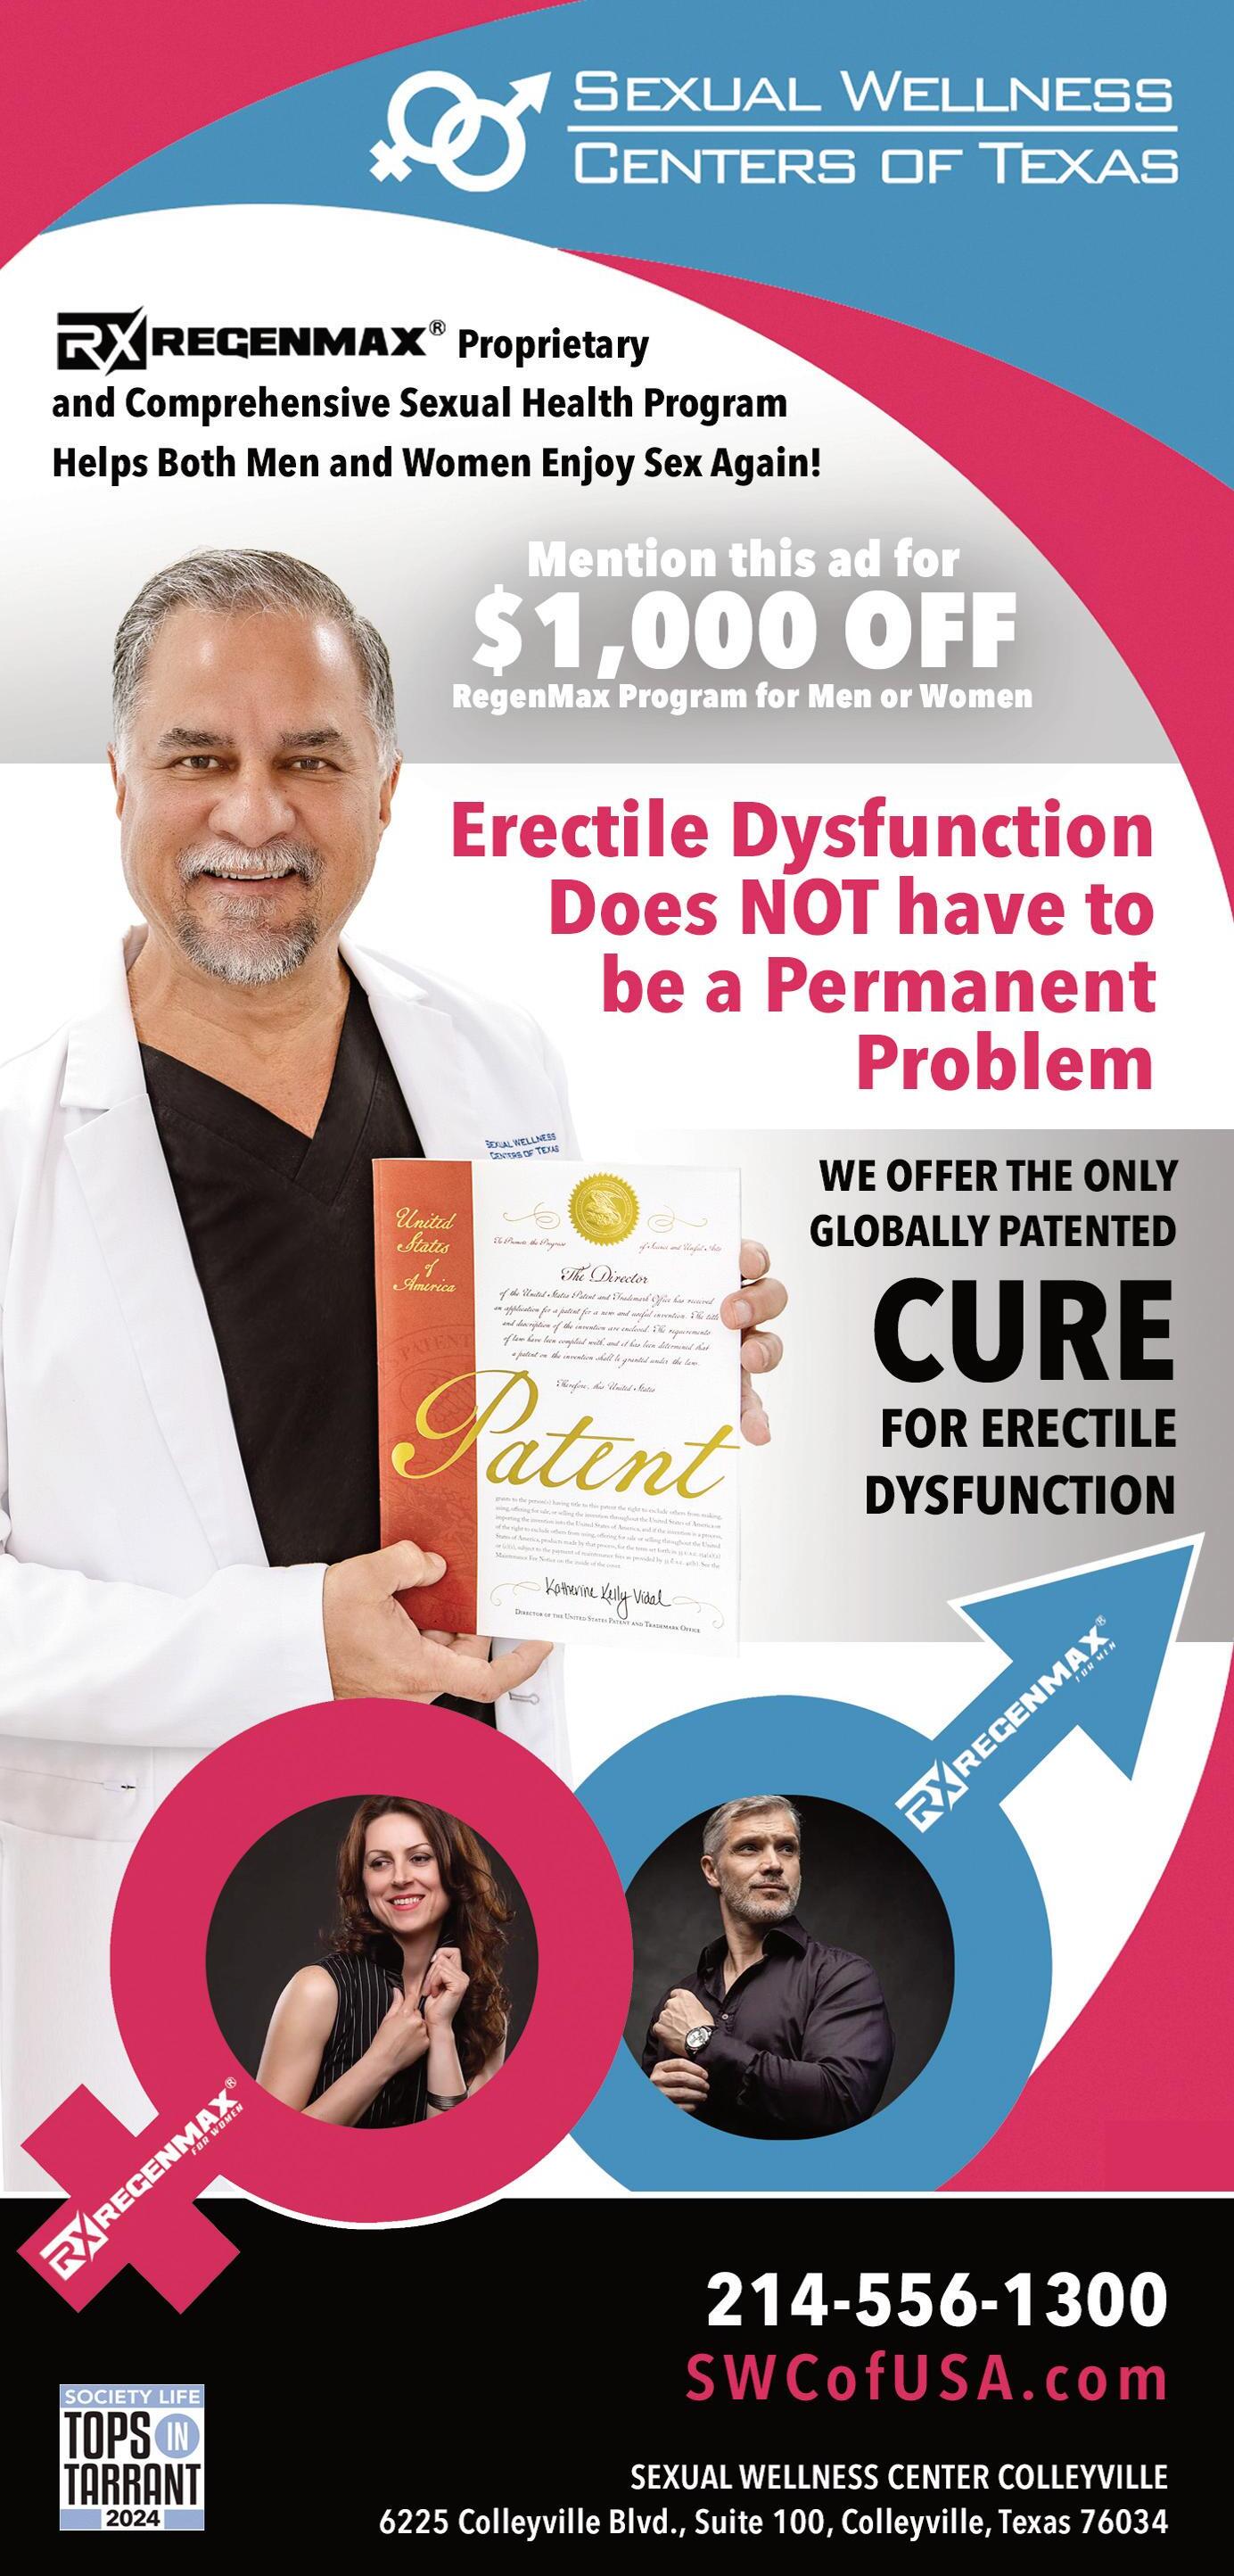

SEXUAL WELLNESS CENTERS OF TEXAS

Specialty | As a medical practice dedicated to sexual health, Sexual Wellness Centers of Texas (SWC) proudly serves patients with patient-focused care and cutting-edge techniques and technologies. SWC was founded with one mission—to rejuvenate your body, boost your energy, increase self-confidence, and help you enjoy your sexuality even in advanced years. Their team is committed to having a holistic approach to caring for, managing, and treating your sexual health. With a commitment to innovation and effective treatment options, SWC is proud to introduce the REGENmax protocol—offering a non-invasive and highly successful cure for ED (erectile dysfunction).

Why Choose SWC | Over the last 15 years and a significant investment in both scientific and clinical studies, a team of SWC MDs and PhDs diligently researched and optimized the REGENmax protocol. Having successfully treated countless patients at their Frisco and Colleyville, Texas locations for years, SWC conducted a formal clinical study of over 250 patients and employed the REGENmax protocol. Results showed 243 patients had reversed their ED after a one-year follow-up, an astounding 97.2% success rate.

REGENmax Protocol | SWC proudly announces the first and only worldwide US patent for the cure of Erectile Dysfunction (ED) and global registered trademark of the REGENmax® protocol. This revolutionary protocol completely reverses ED. You heard that right—it’s a cure. It is important to understand that this is not a pill. It’s not a temporary fix. It’s a painless patent protected procedure with a 97% success rate and quick results.

Life Changing | About 30 million men in the U.S. alone today are suffering from this common issue... they share feelings of hopelessness, shame, worthlessness to themselves and for their partners. ED treatment benefits include a renewed sense of confidence and intimacy for individuals facing challenges with sexual health. Seeking ED treatment not only addresses physical aspects, but also contributes to overall emotional and relational well-being, thus promoting a more fulfilling and satisfying lifestyle.

Patent Protected Procedure | Groundbreaking protocol in a 250-patient study demonstrated effectiveness in eradicating ED—providing a treatment protocol and medical solution for the over 56 million worldwide suffering unnecessarily from this debilitating condition. ED significantly impacts quality of life and self-esteem. Until now, available treatments often relied on pills or surgery, resulting in inconsistent, costly, and temporary results. The REGENmax protocol has solved the root causes of ED through a multi-faceted approach—with absolutely no need for pills or surgical intervention.

Successful Solution | This innovative approach promises to significantly deliver treatment success for ED patients of practice owners, medical providers and clinicians. By integrating REGENmax into their existing protocols, medical practices can offer patients a more cost-effective and non-invasive solution for addressing the root causes of erectile dysfunction.

What You Can Expect | A physical exam and a blood analysis will be performed during your consultation to help the team determine what may be the underlying cause of your sexual dysfunction. Your specific treatment plan will be tailored to meet your unique needs. Some of the available treatments that may be included in your treatment plan include REGENmax for both men and women, HEshot or SHEshot to enhance sexual performance, hormone replacement therapy, ED laser, REGENwave, and more. The goal at SWC is to optimize your personal hormonal levels and this is different for every body.